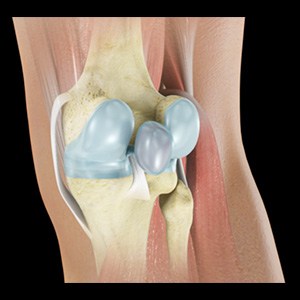

Picture of Meniscal Tears

Meniscal Tears

A meniscal tear is a common knee injury in athletes, especially those involved in contact sports. A sudden bend or twist in your knee causes the meniscus to tear. Elderly people are more prone to degenerative meniscal tears as the cartilage wears out and weakens with age.